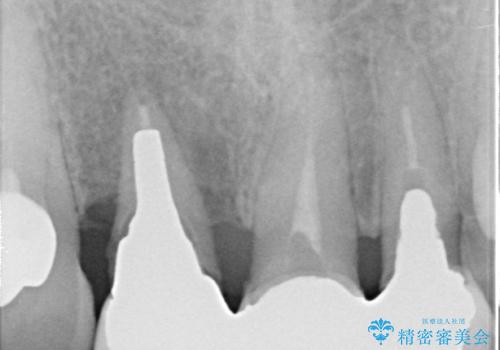

- 下顎前歯部の突き上げで上顎前歯の被せ物が土台ごと外れてしまった方の症例です。

右上1番目の歯は根元まで割れてしまっており、保存不可能だったため抜歯となりました。

抜歯後、骨と歯肉の回復を待ち、オールセラミッククラウンによるブリッジで補綴を行いました。